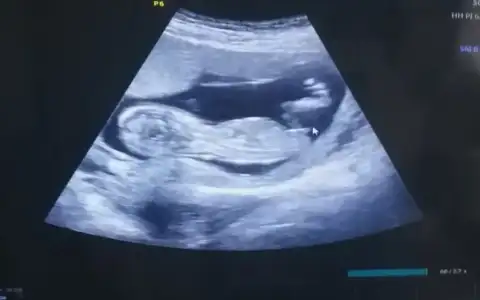

Evet net kız görünüyorMerhaba arkadaşlar 12+4 tahminler var mı dr um %80 Kiz dedi

Kız sanki